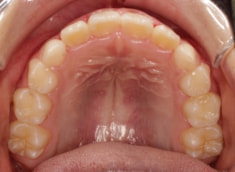

治療後(8ヶ月後)